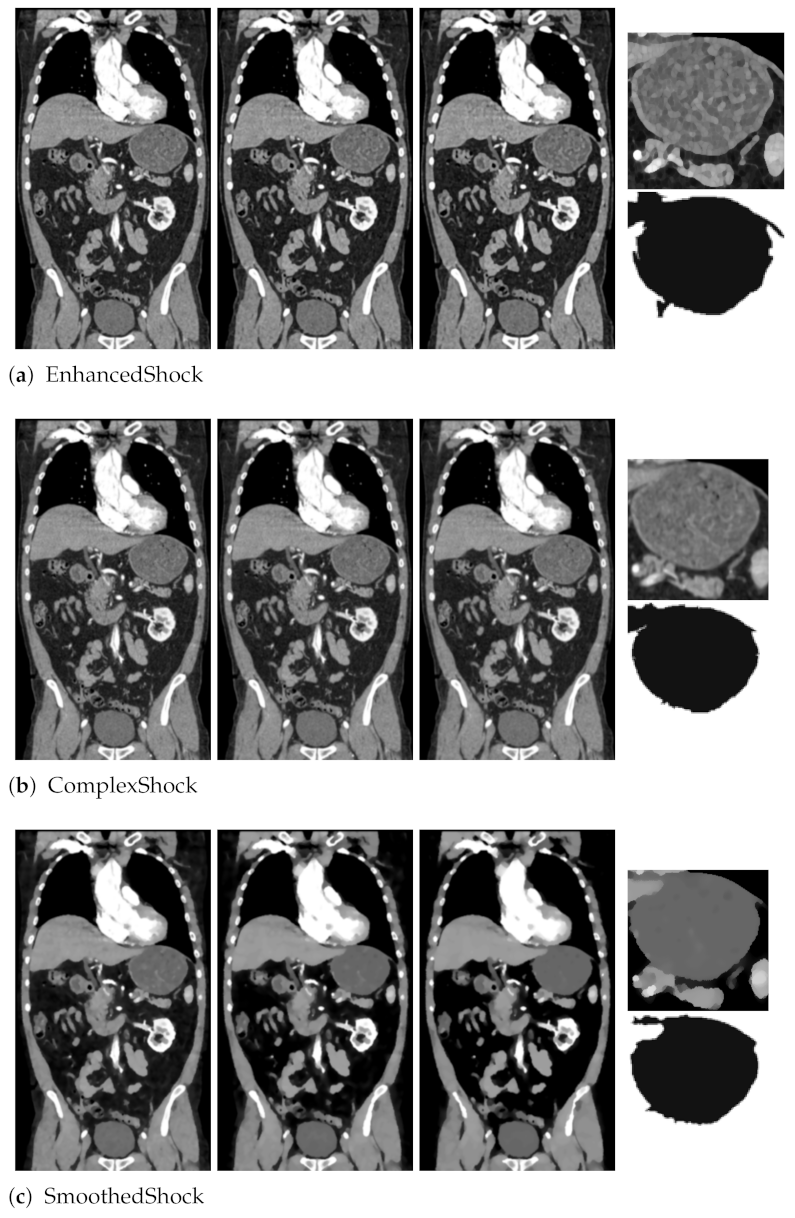

As a preliminary test, we first proposed in [18] to exploit our filter as a pre-processing tool for medical image segmentation. As illustrated in Figure 9, we applied our filter and two others (EnhancedShock and ComplexShock) on a CT scan slice. After 10, 20, and 30 iterations, this evaluation revealed that our algorithm allows enhancing organs’ borders and internal tissues, which leads to an interesting segmentation, with a graph-based algorithm from Felzenszwalb and Huttenlocher [26] applied on images filtered 30 times.

Figure 9.

Segmentation obtained from one CT slice, with different methods, after 10, 20, and 30 iterations. A part of the segmentation is also presented.